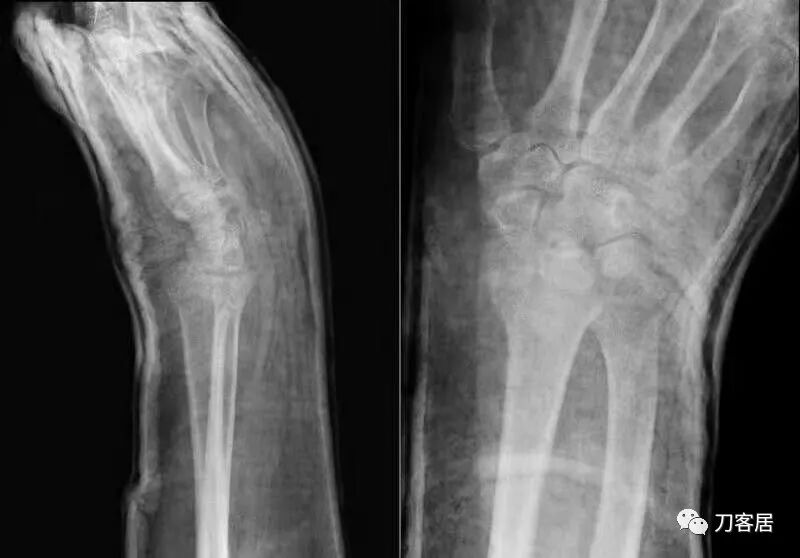

2021年7月22日晚,上海美华医院儿童骨科的师东良医生,给我提供了一例他处理的严重移位尺桡骨双骨折病例,经过手法复位,石膏外固定治愈。这个病例,其他医院建议要做手术。实际上,这样的病例,在现实中有太多太多,因为手法复位,石膏外固定治疗骨折,这是骨科医生的基本功。

下面为师东良医生提供的病例:

超声引导下闭合手法复位石膏外固定治疗7岁患儿尺桡骨远端移位双骨折。

男,7岁,左前臂远端桡尺骨双骨折,术前X光片见图1,行超声引导下闭合复位石膏外固定术,康复训练,6周拆石膏,随访2.5月的效果。术后2.5X光片见图23。功能上仅前臂旋后较健侧减小15°,继续加强康复训练中。家长满意,评价见图4

1. 超声引导下闭合复位石膏外固定术左尺桡骨双骨折

2. 超声引导下闭合复位石膏外固定术后2.5月左前臂正位X光片

3. 超声引导下闭合复位石膏外固定术后2.5月左前臂侧位X光片